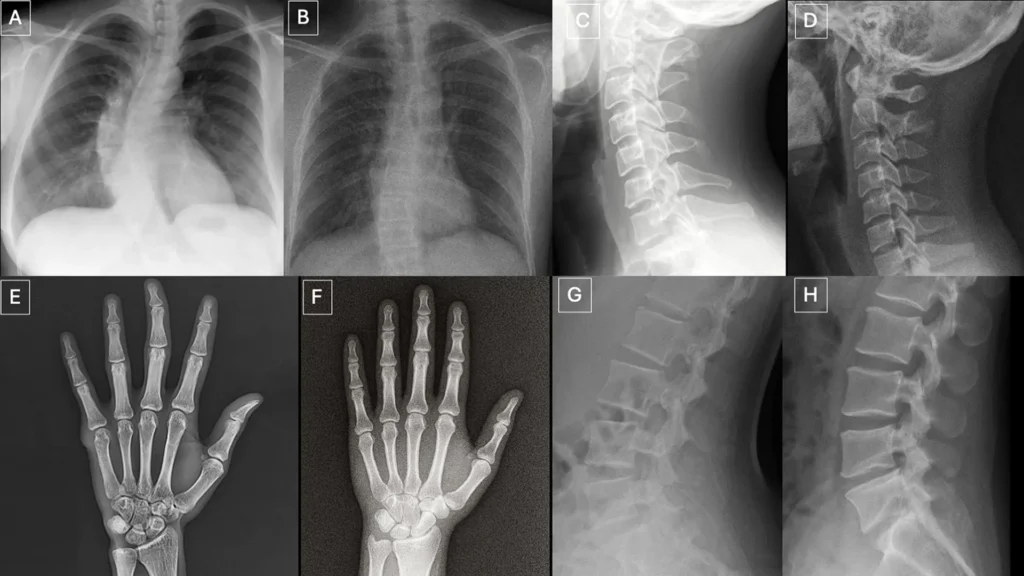

Os pesquisadores identificaram vários padrões que podem aparecer em imagens sintéticas.

“Imagens médicas deepfake geralmente parecem perfeitas demais,” disse o Dr. Tordjman. “Os ossos são excessivamente lisos, as colunas são anormalmente retas, os pulmões são excessivamente simétricos, os padrões de vasos sanguíneos são excessivamente uniformes e as fraturas aparecem incomumente limpas e consistentes, frequentemente limitadas a um lado do osso.”